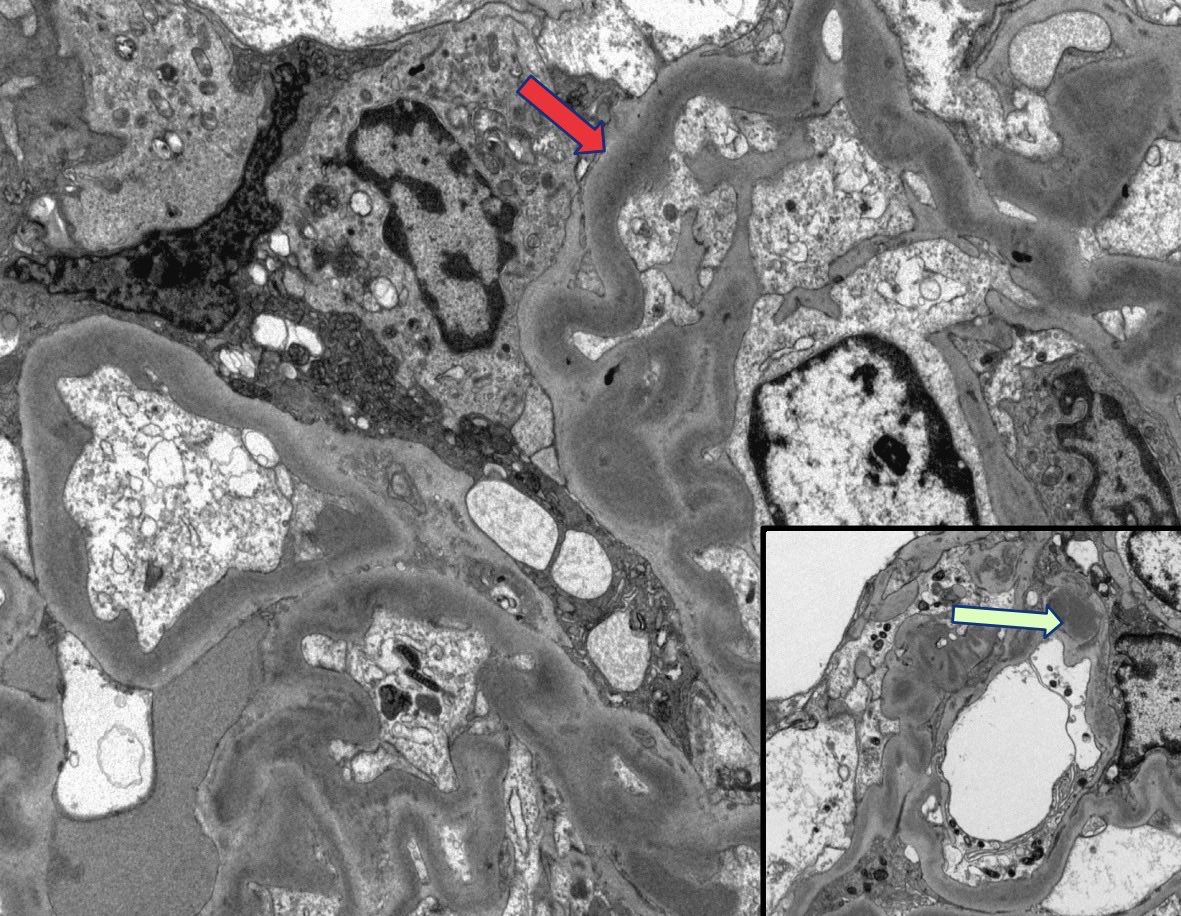

Mini case-series of crystal-storing histiocytosis (CSH) affecting predominantly glomerular loops with detailed literature review of renal CSH, images of one of the cases are depicted below, authors.elsevier.com/c/1Zh4S3uV~y8B…